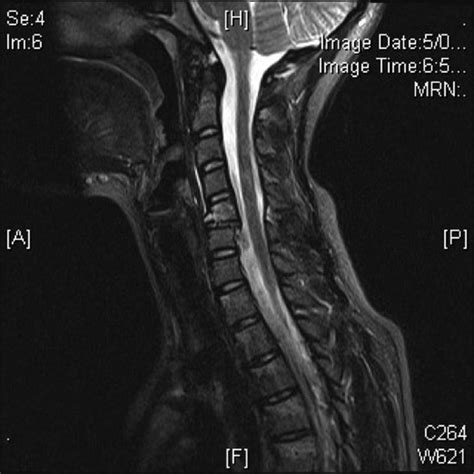

• Magnetic Resonance Imaging (MRI): Crucial for assessing the extent of spinal cord injury and identifying soft tissue damage, such as ligamentous tears (specifically the posterior ligamentous complex).

The name of the injury stems from the specific mechanism of action: hyperflexion. When the neck is forced into an extreme forward-bending position while simultaneously experiencing axial loading (a downward force), the cervical vertebrae are crushed. This combined force causes the anterior portion of the vertebral body to shear off. Unlike simple compression fractures, the Flexion Teardrop Fracture is inherently unstable, often causing the vertebral body to be displaced posteriorly into the spinal canal.

This displacement is what makes this specific fracture so dangerous. When the posterior aspect of the fractured vertebra moves backward, it frequently compresses the spinal cord, leading to a condition known as Anterior Cord Syndrome. Patients suffering from this syndrome may experience: